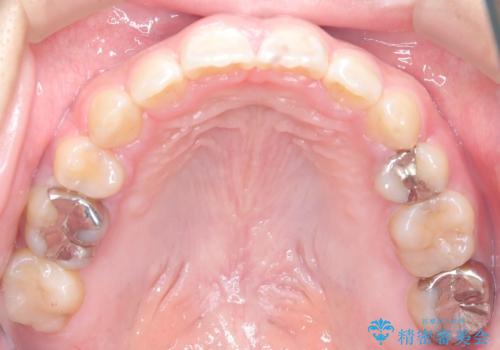

- 口元が出ている(突出している)ことを気にされて来院されました。精密な検査の結果、前歯を大きく後退させるスペースが必要と診断。患者様の**「前歯を下げたい」という強いご要望に応えるため、上下左右の第一小臼歯を抜歯し、そのスペースを利用して前歯を奥へ移動させる治療計画を立案しました。また、人目を気にせず治療できるよう、上顎に裏側矯正、下顎に表側矯正を組み合わせたハーフリンガル矯正**を提案しました。

今回の矯正治療では、前歯を大きく後退させるスペースを確保するため、計画通り上下左右の第一小臼歯を抜歯しました。装置には、上顎には目立たない裏側矯正(舌側矯正)を、下顎には透明な審美ブラケットを使用するハーフリンガル矯正を採用しました。抜歯によってできたスペースを最大限に活用し、前歯を効率よく後方へ移動。治療の結果、口元の突出感が大幅に解消され、Eライン(横顔の美しさの基準)も改善しました。人目を気にすることなく治療を完遂し、自信の持てる美しい横顔を獲得していただけました。